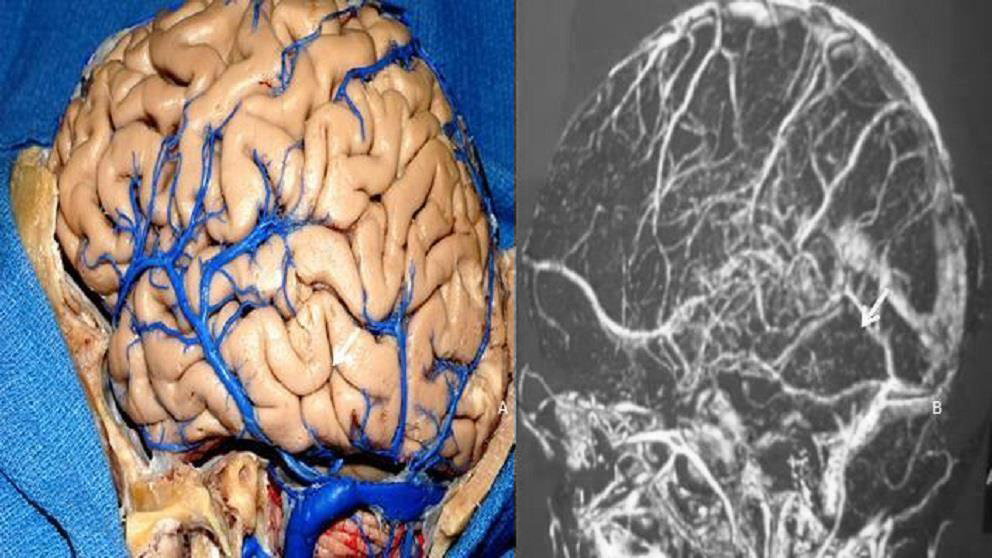

Figura 13: El estudio de la posición del drenaje de la vena anastomótica inferior (Labbé) se realiza para evaluar cuando se pretende realizar el abordaje petroso posterior. La vena de Labbé comúnmente drena en la unión de los senos transverso y sigmoideo (flecha). Pieza anatómica (A). Resonancia venosa (B).